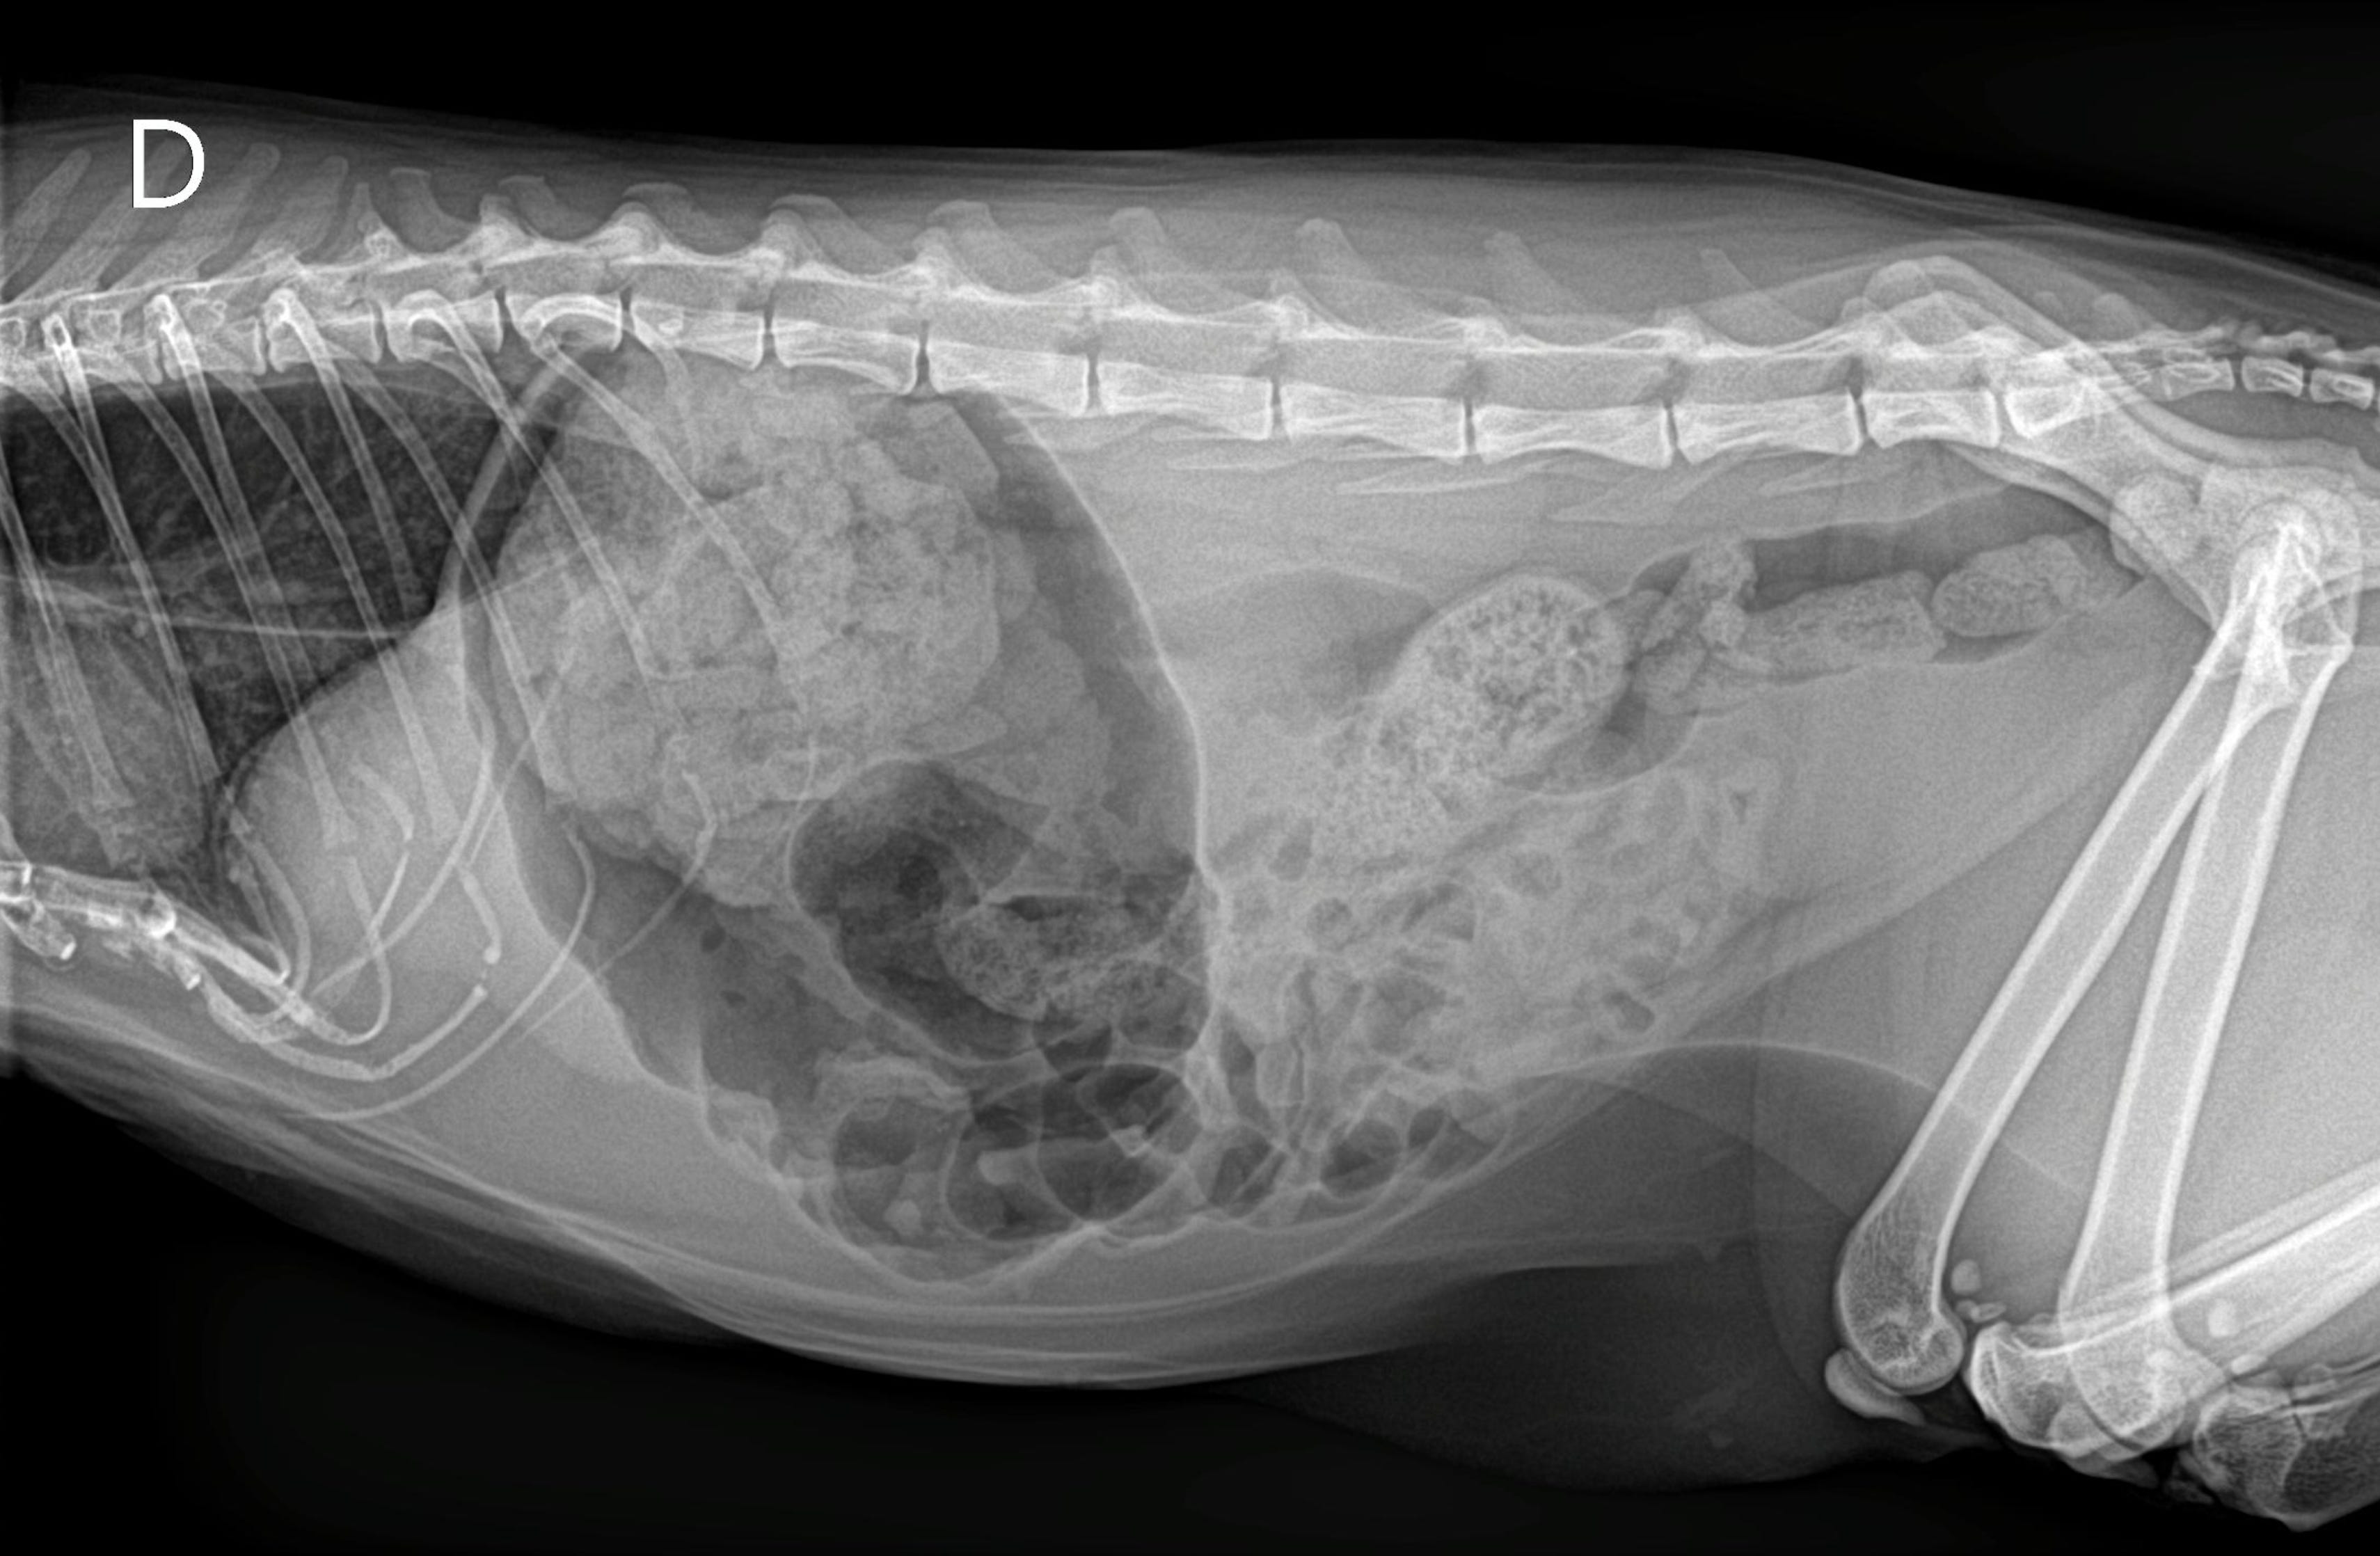

Hacemos un pequeño paréntesis. Arya presentó la semana previa a esta consulta con signos digestivos más acusados (vómitos / regurgitación). Esta eran sus radiografías, donde si no conociéramos el caso podríamos sospechar de un proceso digestivo obstructivo (puedes apreciar incluso megaesófago en la porción visible):

Estas imágenes en combinación con la patología respiratoria de Arya ilustra un bonito ejemplo de “síndrome aerodigestivo”. Recordemos que este síndrome describe la interacción patológica entre el tracto respiratorio superior y el tracto digestivo superior (faringe, laringe, esófago).

En gatos, cuando existe una estenosis nasofaríngea, se puede producir una disfunción aerodigestiva secundaria, ya que las alteraciones en el flujo aéreo nasal y faríngeo modifican la fisiología normal de la deglución, la presión intratorácica y la coordinación respiratoria-digestiva.